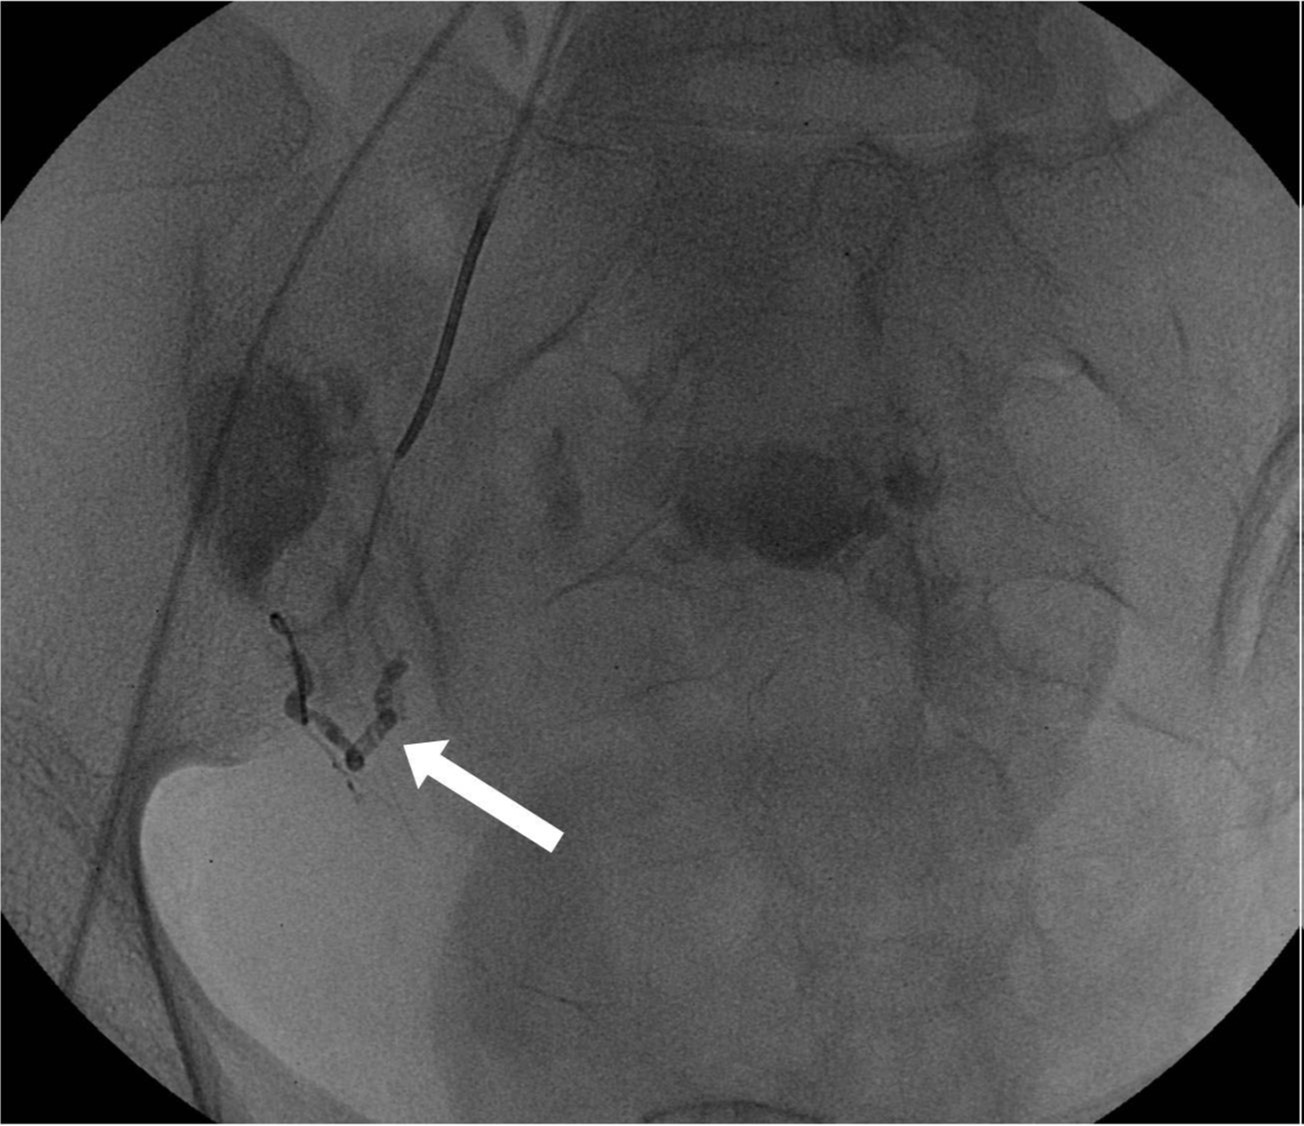

Fig. 2.

The mixture of N-butyl-2-cyanoacrylate and lipiodol with a ratio of 1:3 was injected at the tip of a microcatheter, but it did not reach to the rupture point. The proximal part of the right uterine artery was only embolized (arrow).